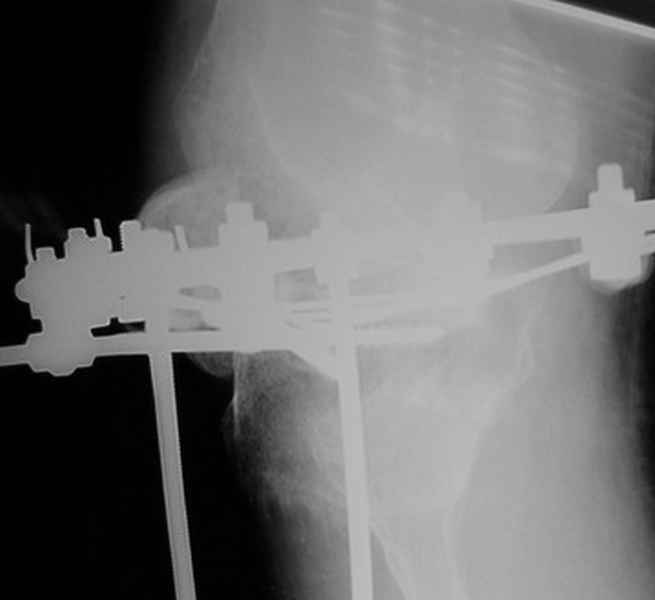

Пациент В. 53 лет, травма в феврале 2009. ДЗ. Открытый оскольчатый перелом нижней трети голени. При боли поступлении выполено ПХО, аппарат Илизарова. В последующем проводили ВХО, резекция костных отломков, укорочение 6 см, рана зажила. Была выполнена остеотомия большеберцовой кости в проксимальном отделе, резекция. Производилось тракция. На последних рентгенограммах выявлено, что одновременно с "выращиванием" регенерата произошло низведение надколенника на длину выращенного регенерата. Клинически: активное разгибание сохранено, объем движений в колене 180-110 градусов. Черными стрелками обозначен верхний край надколенника с одной и с другой стороны. Красная стрелка обозначает пальпируемую связку надколенника. Причина - остеотомия выше места прикрепления связки надколенника. Вопрос: была ли у кого подобная ситуация? Что делать? При первом обдумывании приходит решение: отсечение места прикрепления связки надколенника с костным блоком, перемещение на "правильное" место, укорочение сухожилия четырехглавой мышцы.

По снимкам - плотность регенерата хорошая, сложностей с фиксацией в него костного "основания" быть не должно.

Я бы уменьшил диастаз между фрагментами сантиметра на два. Судя по снимкам, регенерат это может позволить.

Я бы присоединился к предложению А.Артемьева - уменьшить диастаз, и посмотреть можно будет, как поведет себя надколенник.

Чтобы не сталкиваться с таким осложнением, лучше удлинять большеберцовую кость на уровне диафиза. Тогда еще и интрамедуллярный стержень будет удобнее вводить по завершении удлинения ;-)